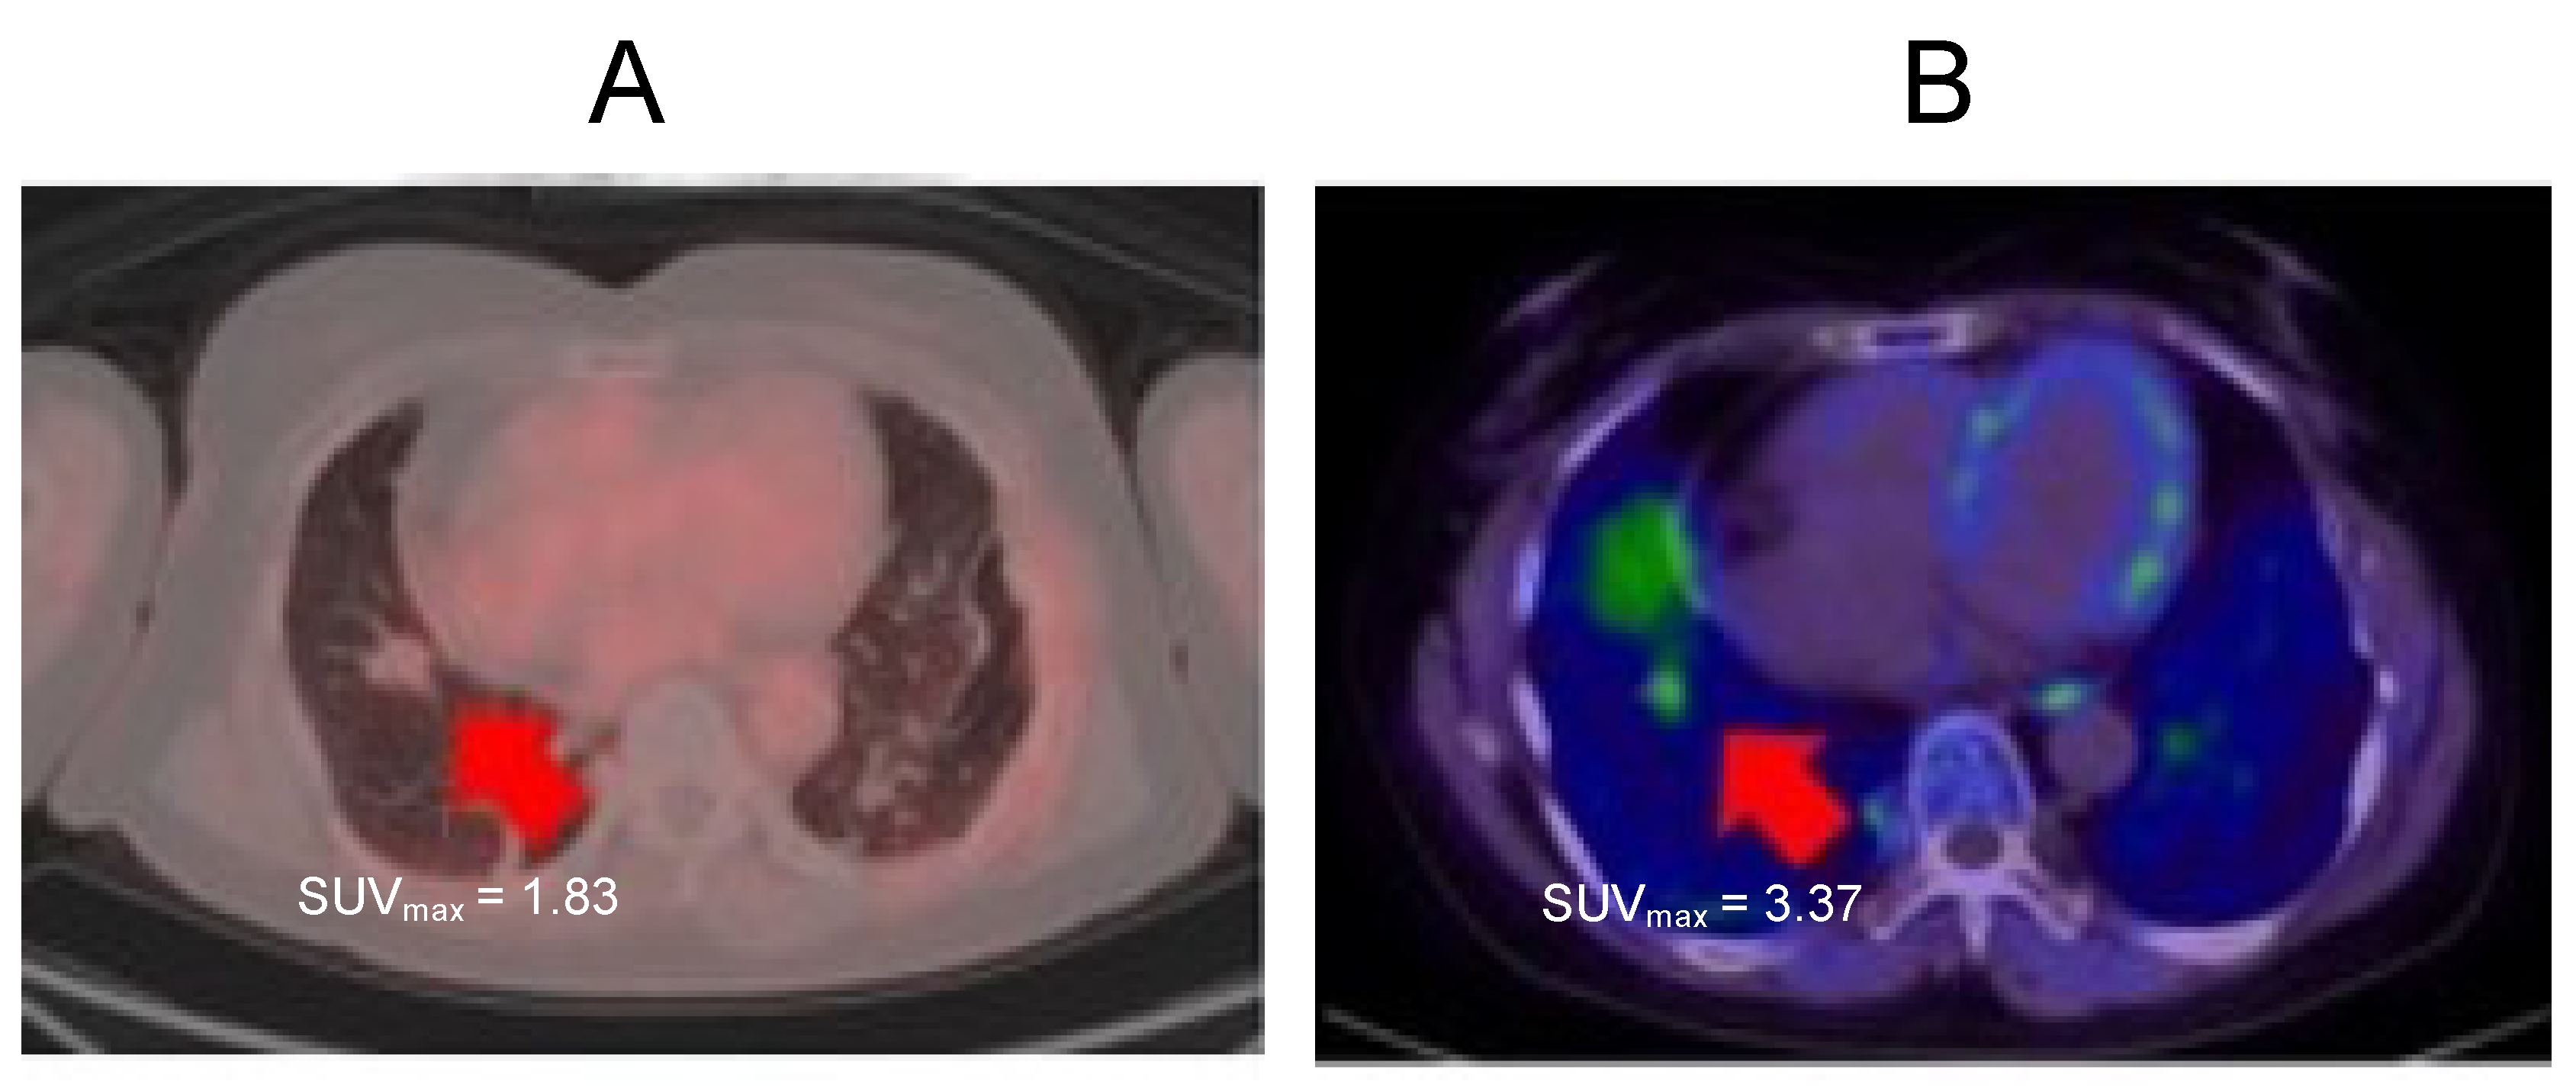

2.3. Case 3

2.4. Case 4